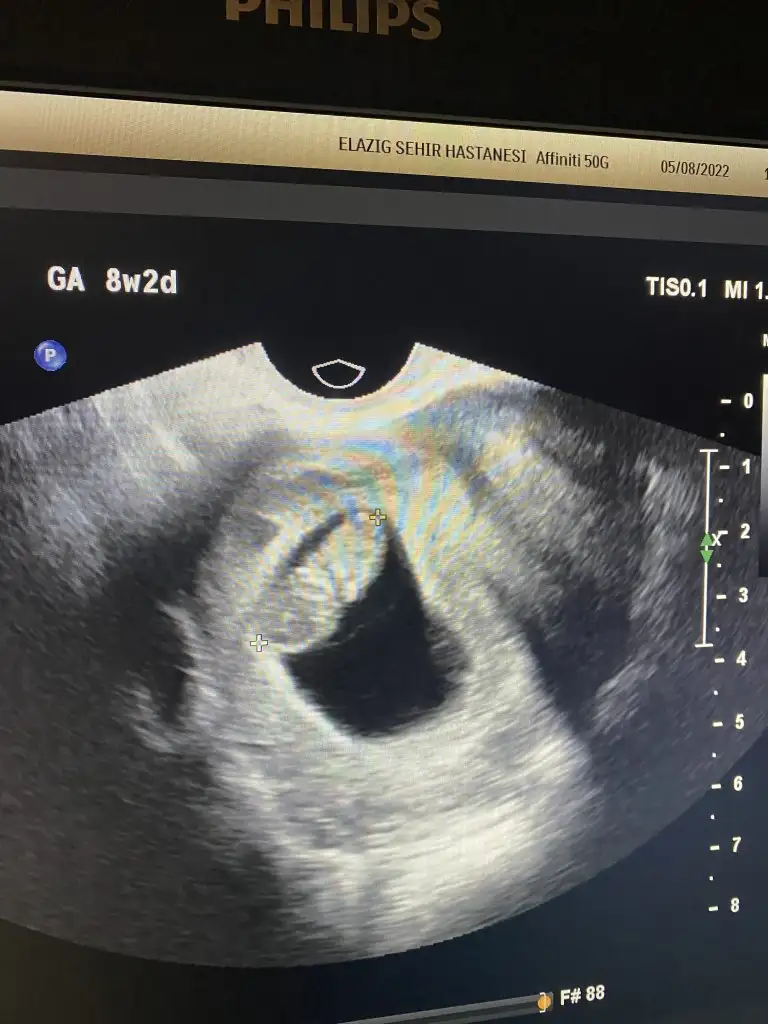

Herkese hayırlı olsun, sağlıklı olsunda insan merak ediyor işte banada yorum yapar mısınız 6 haftalık vajinal ultrason